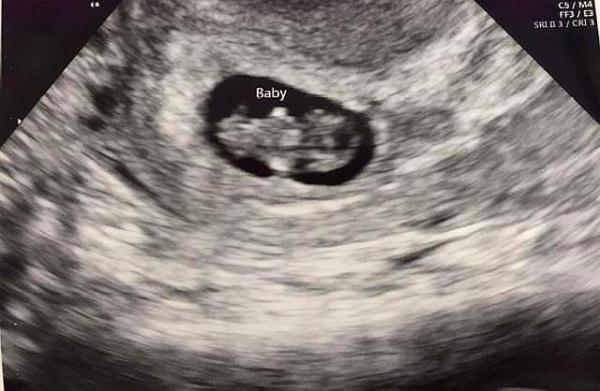

B超检查,指标都合格:在第1次产检时,是必须要进行B超检查的,既是为了有效观测胎儿的发育状况,又是为了有效排除宫外孕问题。

在怀孕一个月左右时,子宫内已经形成了孕囊是怀孕最初的一个形态,而孕囊的尺寸大约在1.33~1.66厘米之间,如若你已经超过了怀孕一个月进行B超检查时,还可能会听到胎心,但是胎心率不稳。如若这几个指标都能够正常,说明胎儿正在健康发育。